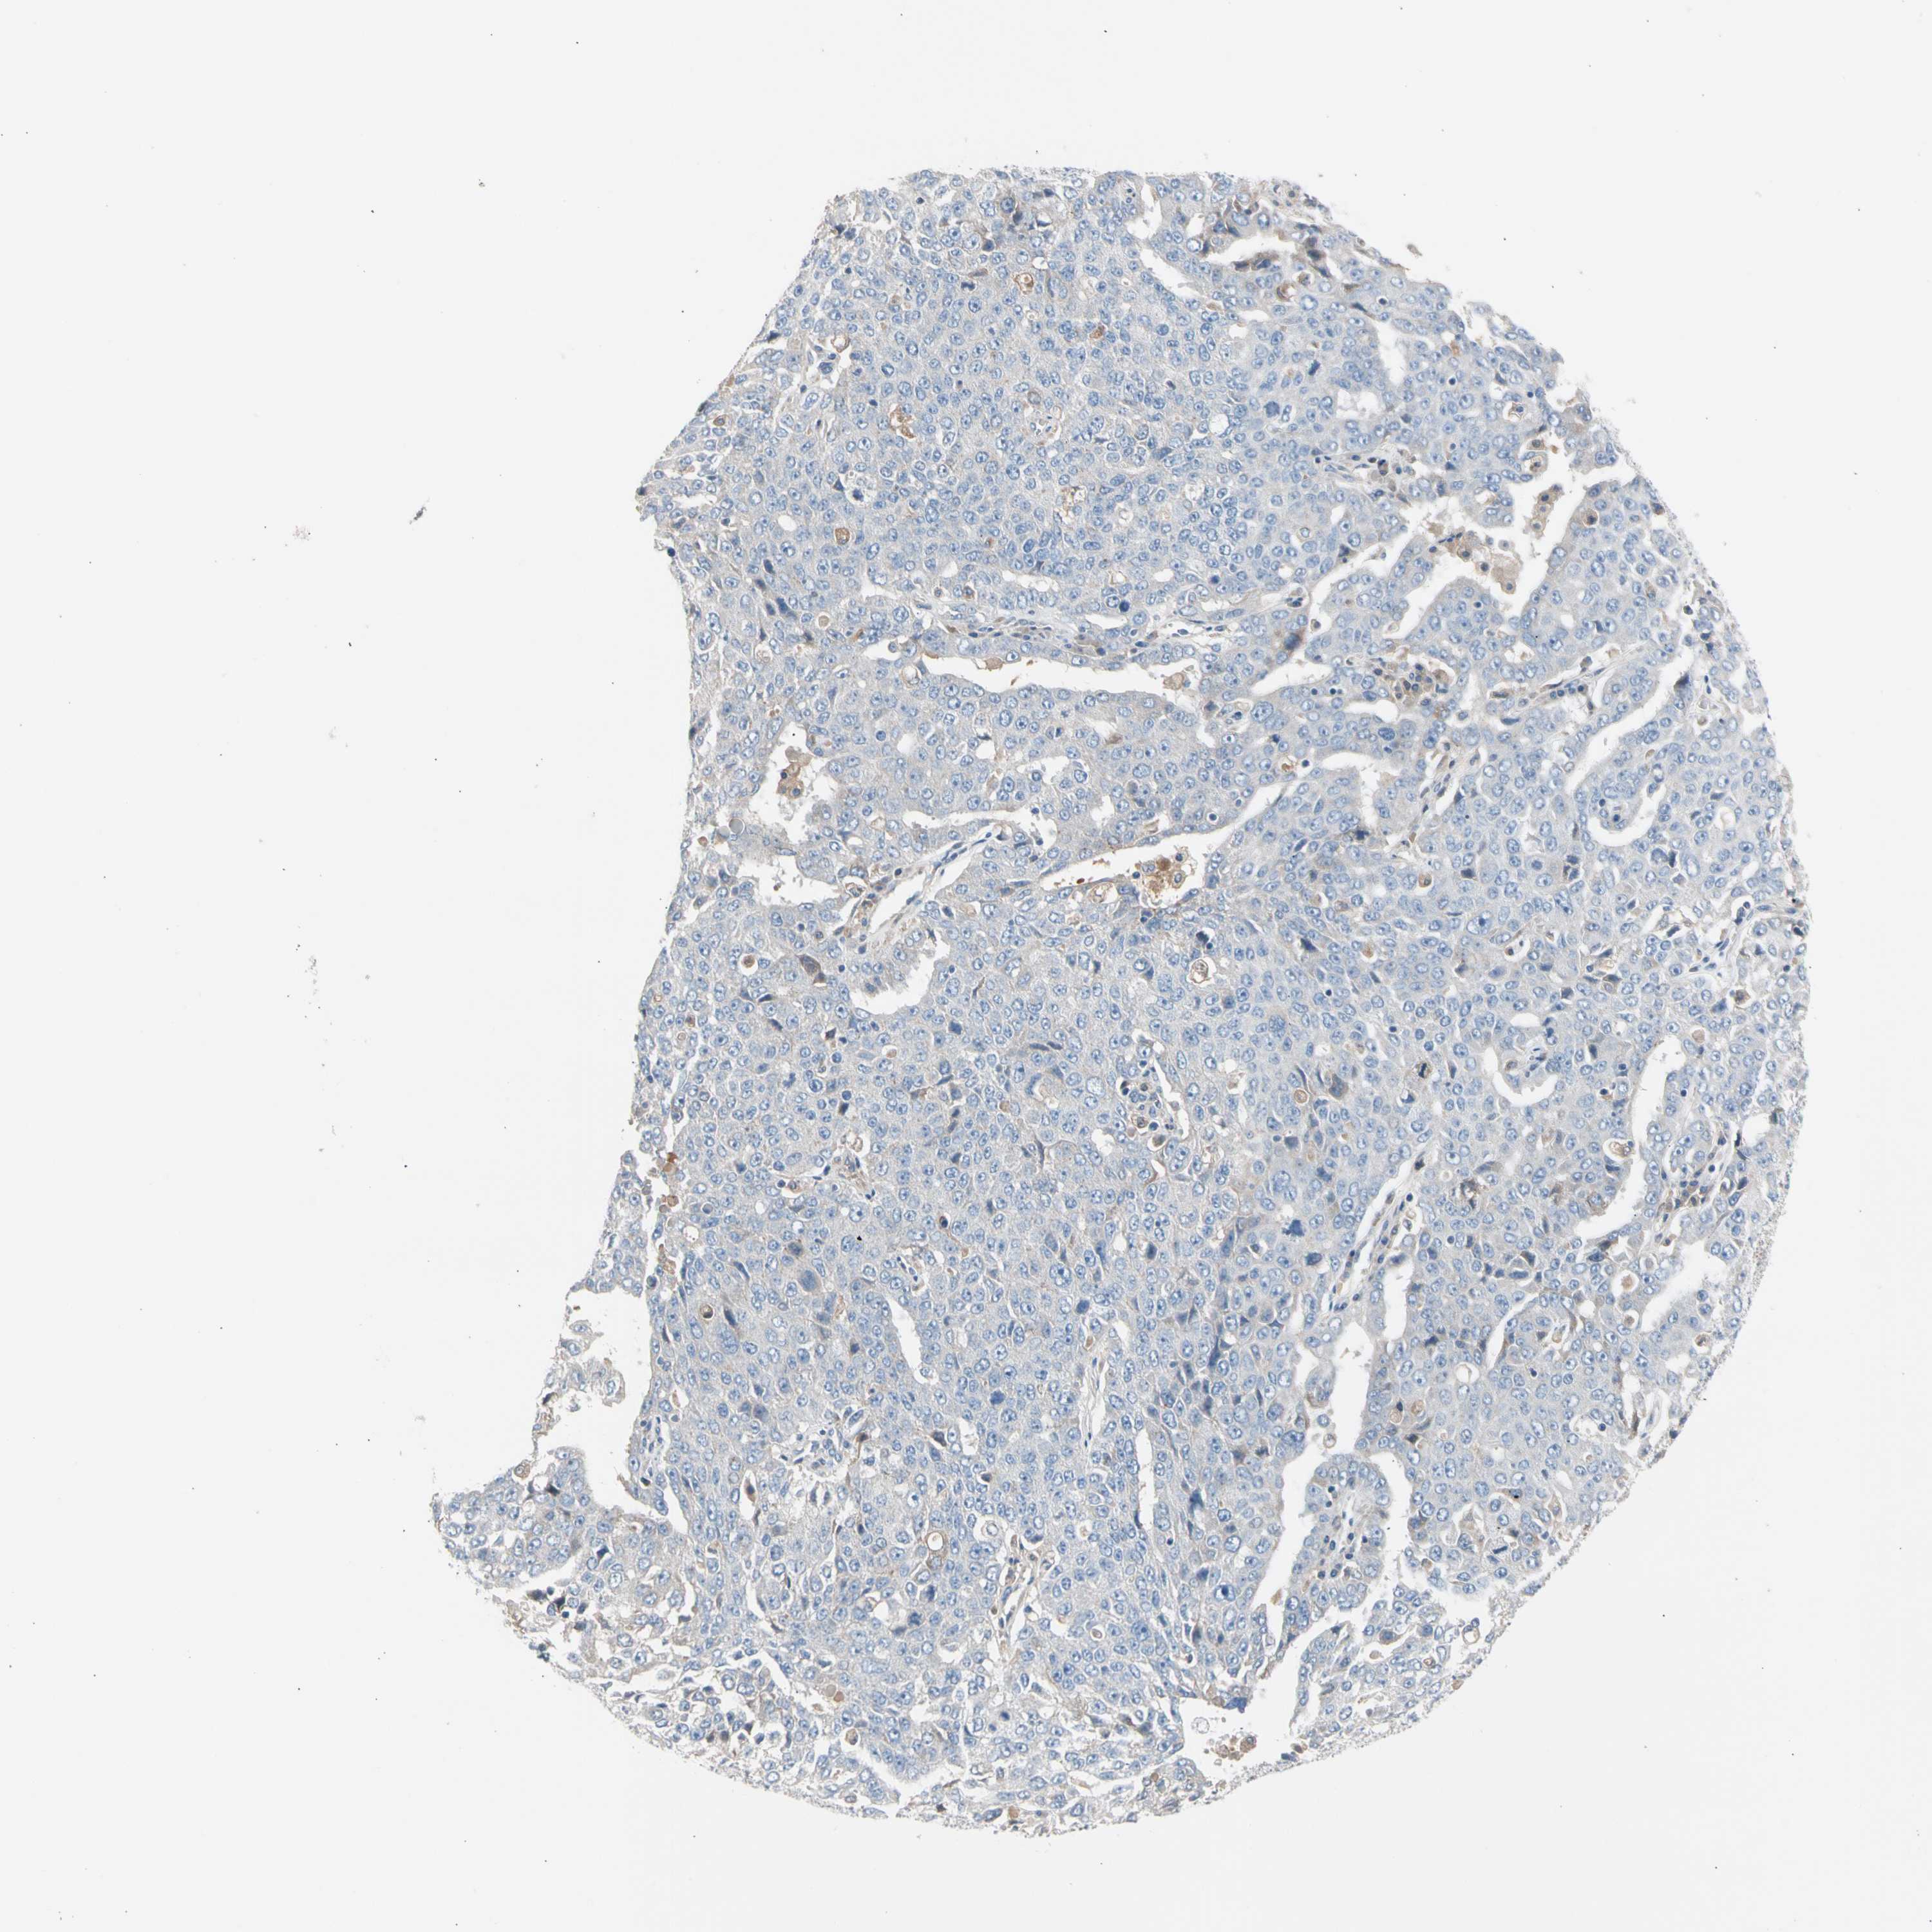

OVARIAN CANCER - Protein expressioni

A mouse-over function shows sample information and annotation data. Click on an image to view it in a full screen mode. Samples can be filtered based on level of antibody staining by selecting one or several of the following categories: high, medium, low and not detected. The assay and annotation is described here.

Note that samples used for immunohistochemistry by the Human Protein Atlas do not correspond to samples in the TCGA dataset.

Antibody stainingi

Antibody staining in the annotated cell types in the current human tissue is reported as not detected, low, medium, or high, based on conventional immunohistochemistry profiling in selected tissues. This score is based on the combination of the staining intensity and fraction of stained cells.

Each image is clickable and will lead to virtual microscopy that enables deeper exploration of all samples and also displays staining intensity scores, fraction scores and subcellular localization as well as patient and tissue information for each sample.

Antibody HPA007845

Antibody HPA026823

Antibody CAB015170

Staining

High

Medium

Low

Not detected

Cystadenocarcinoma, serous, NOS

Carcinoma, endometroid

Cystadenocarcinoma, mucinous, NOS

Carcinoma, NOS